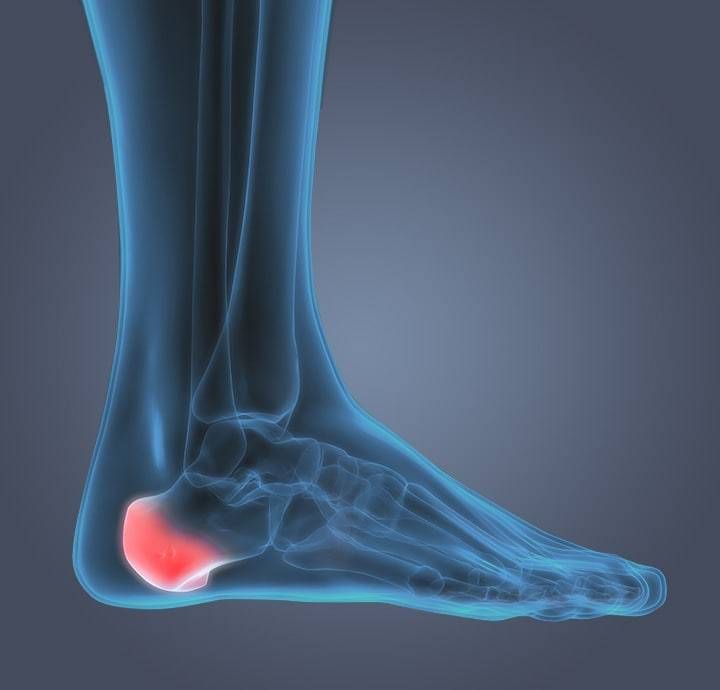

Lower limb fractures and dislocations

Lower limb refers to the part of our body starting from the hips upto the toes in our feet. This part of our body helps us to walk, run and in our day-to-day movement and activities. Hence injuries to the structures in our thigh / leg / feet is common. Knee and ankle joint dislocations are seen in high velocity road traffic collisions and are extremely serious injuries with potential risk of loss of limb from amputation.

Management of lower limb fractures and dislocations needs a systematic approach with thorough evaluation of all the factors to help provide the best treatment to the patients. Treatment depends on the type and severity of trauma and can involve medications such as painkillers, splints / braces and surgery to treat the injury to the bone and soft tissues.